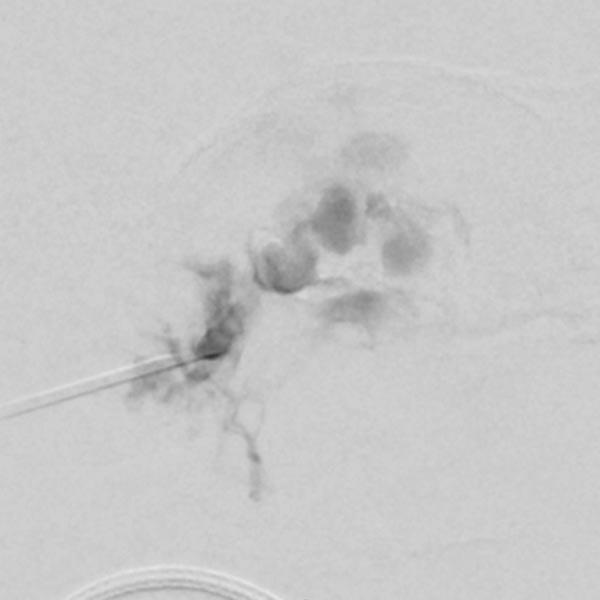

Aufgrund der starken Perfusion der Raumforderung sowie der Ausdehnung in die Orbita wird präoperativ eine Embolisation mit Ethylen-Vinyl-Alkohol-Kopolymer in Direktpunktionstechnik durchgeführt. DSA nach Direktpunktion mit venöser Drainage.

Das Röntgendurchleuchtungsbild zeigt das Embolisat innerhalb der Gefäße schwarz (röntgendicht). Es gelingt superselektiv die Perfusion im Hämangiom stark zu vermindern.